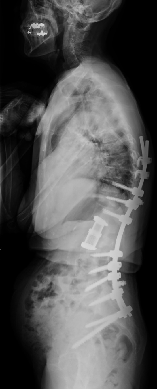

思春期特発性側弯症の全脊椎レントゲンで背骨が大きくSの字に曲がっています。最も曲がっている箇所は80°で、高度側弯に分類されます。後方からの脊柱側弯矯正術で真っ直ぐになっています。

また、側弯の患者さんは一般的にフラットバックと言って背骨の生理的後弯(背中の丸み)が失われています。この症例も胸椎後弯角は5°で典型的なフラットバックを呈しています(正常は20°~30°程度です)。この影響は頸椎の形態にも影響を及ぼし、この症例も頸椎が既に後弯(正常は前弯)しています。(黄色矢印)

ストレートネックという頸椎の前弯が消失して頸部の愁訴が出現する病態は広く知られていますが、更に変形が進行した頸椎と考えて下さい。

以前はこのフラットバック(生理的胸椎後弯の消失)を治すことは困難でしたが、当院では手術方法の様々な工夫により生理的胸椎後弯の復元を行っております。この症例は術後に胸椎後弯角が26°と改善しており、生理的な胸椎後弯が形成されています。さらに頸椎後弯にも良い影響を及ぼし、術後は頸椎前弯化が得られつつあるのが分かります。(黄色矢印)

他、側弯変形は必ず大なり小なりの回旋変形を伴います。脊柱の回旋変形は胸郭(肋骨)の回旋につながり、これにより側弯の患者さんは背中の片方が出っ張っています(多くは右)。リブハンプと言いますが、脊柱変形矯正によりこの回旋変形も改善します。この症例も術前に肋骨がかなり隆起していますが、術後にこの隆起がかなり減じているのが分かります。(赤矢印)